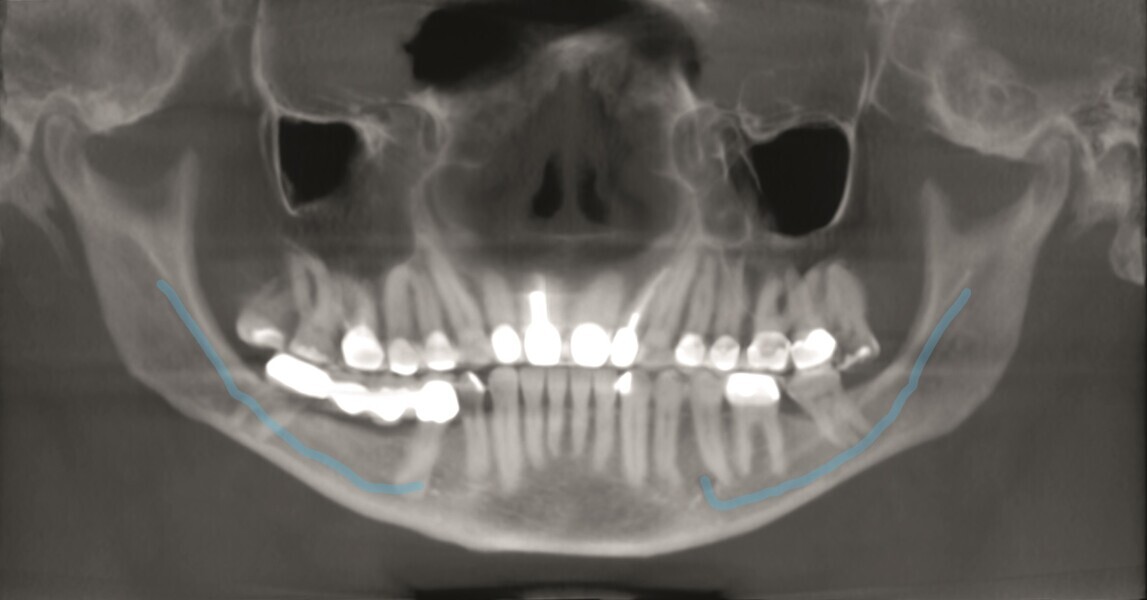

Ce patient m’a consulté en urgence pour une douleur aiguë affectant une deuxième molaire supérieure. Après un examen clinique confirmatoire, une radiographie standard (Fig. 1) a révélé une anatomie très complexe et une calcification pulpaire.

J’ai décidé d’utiliser le système d’imagerie i-CAT, afin de mieux comprendre ce qui se passait. Par comparaison avec la cavité pulpaire de la première molaire, l’examen de la coupe dans le plan horizontal a clairement montré la présence d’une calcification pulpaire de la deuxième molaire (Fig. 2).